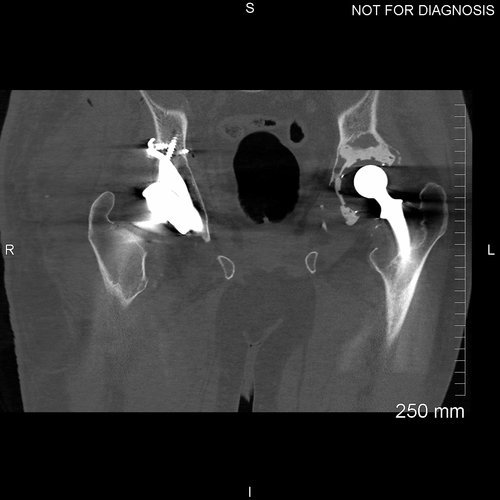

Post-operative CT scan to assess the position of the implant within the bony pelvis

Post-operative EOS images demonstrate the functional position of the acetabular implant. Note the level of the knees and the flat pelvis, demonstrating that there is no leg length discrepancy post-op